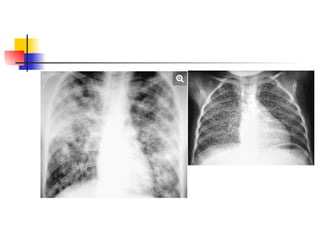

 2 patterns of distribution occur: 1. Segmental or lobar 2.

“batswing”.

 Bats wing occurs typically in pulmonary oedema. It is non-

segmental.

 Air bronchograms may be visible.

Describe what is shown on these

pts with alveolar shadowing!